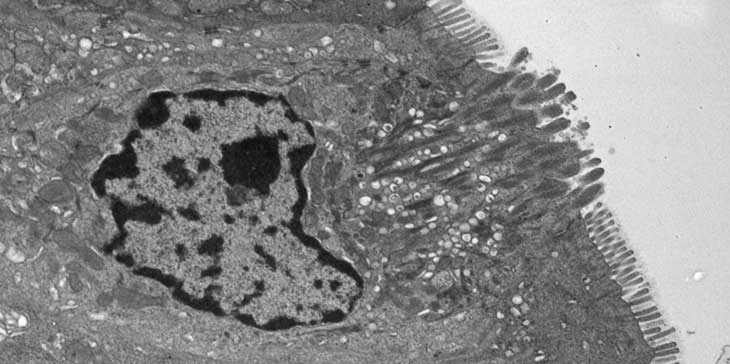

THE WINNER IS… In mice, norovirus invades tuft cells (the two bright green spots) in the lining of the small intestine (left) and the colon (right). Other cells in the intestines that weren’t infected (blue) are also shown.

C. Wilen et al/Science 2018